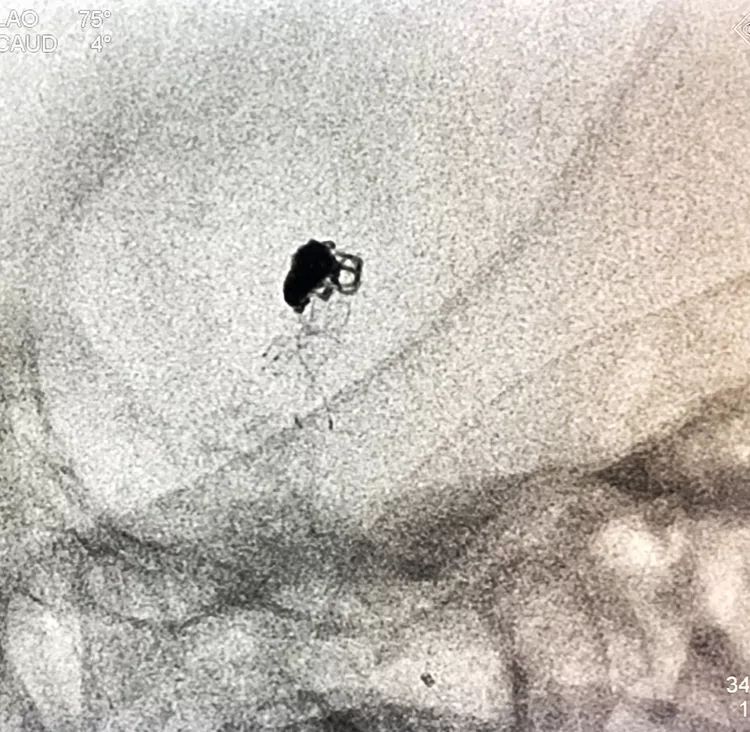

再投入一枚1.5-3的小圈

继续钻入一枚1.5-2的小圈

嗯,完美收官!